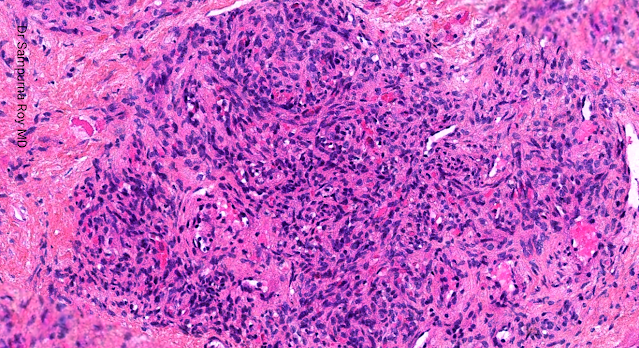

Dermatopathology Case 205 Get link Facebook X Pinterest Email Other Apps April 21, 2022 2 year old child with a painful, erythematous nodule on the right shoulder. Answer Get link Facebook X Pinterest Email Other Apps Comments